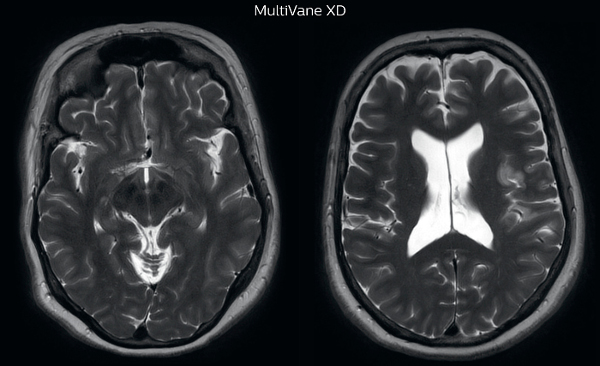

MRI motion artifact reduction in brain

The images made with MultiVane XD show significant reduction in motion artifact compared to the T2-weighted images without MultiVane below them.

Scanned on Ingenia 3.0T

Diagnostic imaging in presence of motion

“Motion artifacts can obscure subtle findings, make image interpretation more difficult and decrease diagnosis confidence. For example, when imaging the cerebellum or brain stem, or when looking for subtle multiple sclerosis (MS) lesions, motion can be problematic,” says Dr Nickerson.

MultiVane XD motion-free imaging delivers diagnostic images even in the case of severe patient motion. A more relevant patient group is one with typical small artifacts related to moderate motion like an occasional cough. The absence of those artefacts brings forth better day-to-day diagnostic confidence. MultiVane XD works in multiple orientations and for various contrasts, such as T1-weighted, T2 weighted and FLAIR.

Trevor Andrews, PhD, explains that the team compared motion artifacts seen in the brain with MultiVane XD and with T2-weighted TSE. “In nine out of the ten datasets in our studywe saw clear improvementswith MultiVane XD, while in the tenth dataset image qualitywas comparable. The MultiVane XD sequence is now used in the majority of patients that present at UVM for brain MRI.”

Motion-free imaging of white matter changes with MultiVane XD

“We saw MultiVane XD provide remarkable improvement, not only for artifacts caused by patient motion, but also for the extent of pulsation artifacts in the basal cisterns. Based on these results, we have added the MultiVane XD sequence to our brain studies,” says Dr. Nickerson.

“MultiVane XD is especially useful when imaging patients with diseases that cause white matter changes on T2-weighted images, such as MS, small vessel disease, vasculitis and sarcoidosis,” says Dr. Nickerson. “Many of these are only visible on T2-weighted or FLAIR images, and sometimes aren’t even seen with FLAIR images. However, when using MultiVane XD and we don’t see any motion on the rest of the scan, but still do see a signal abnormality, we can probably attribute that to a real disease process, rather than an artifact.”